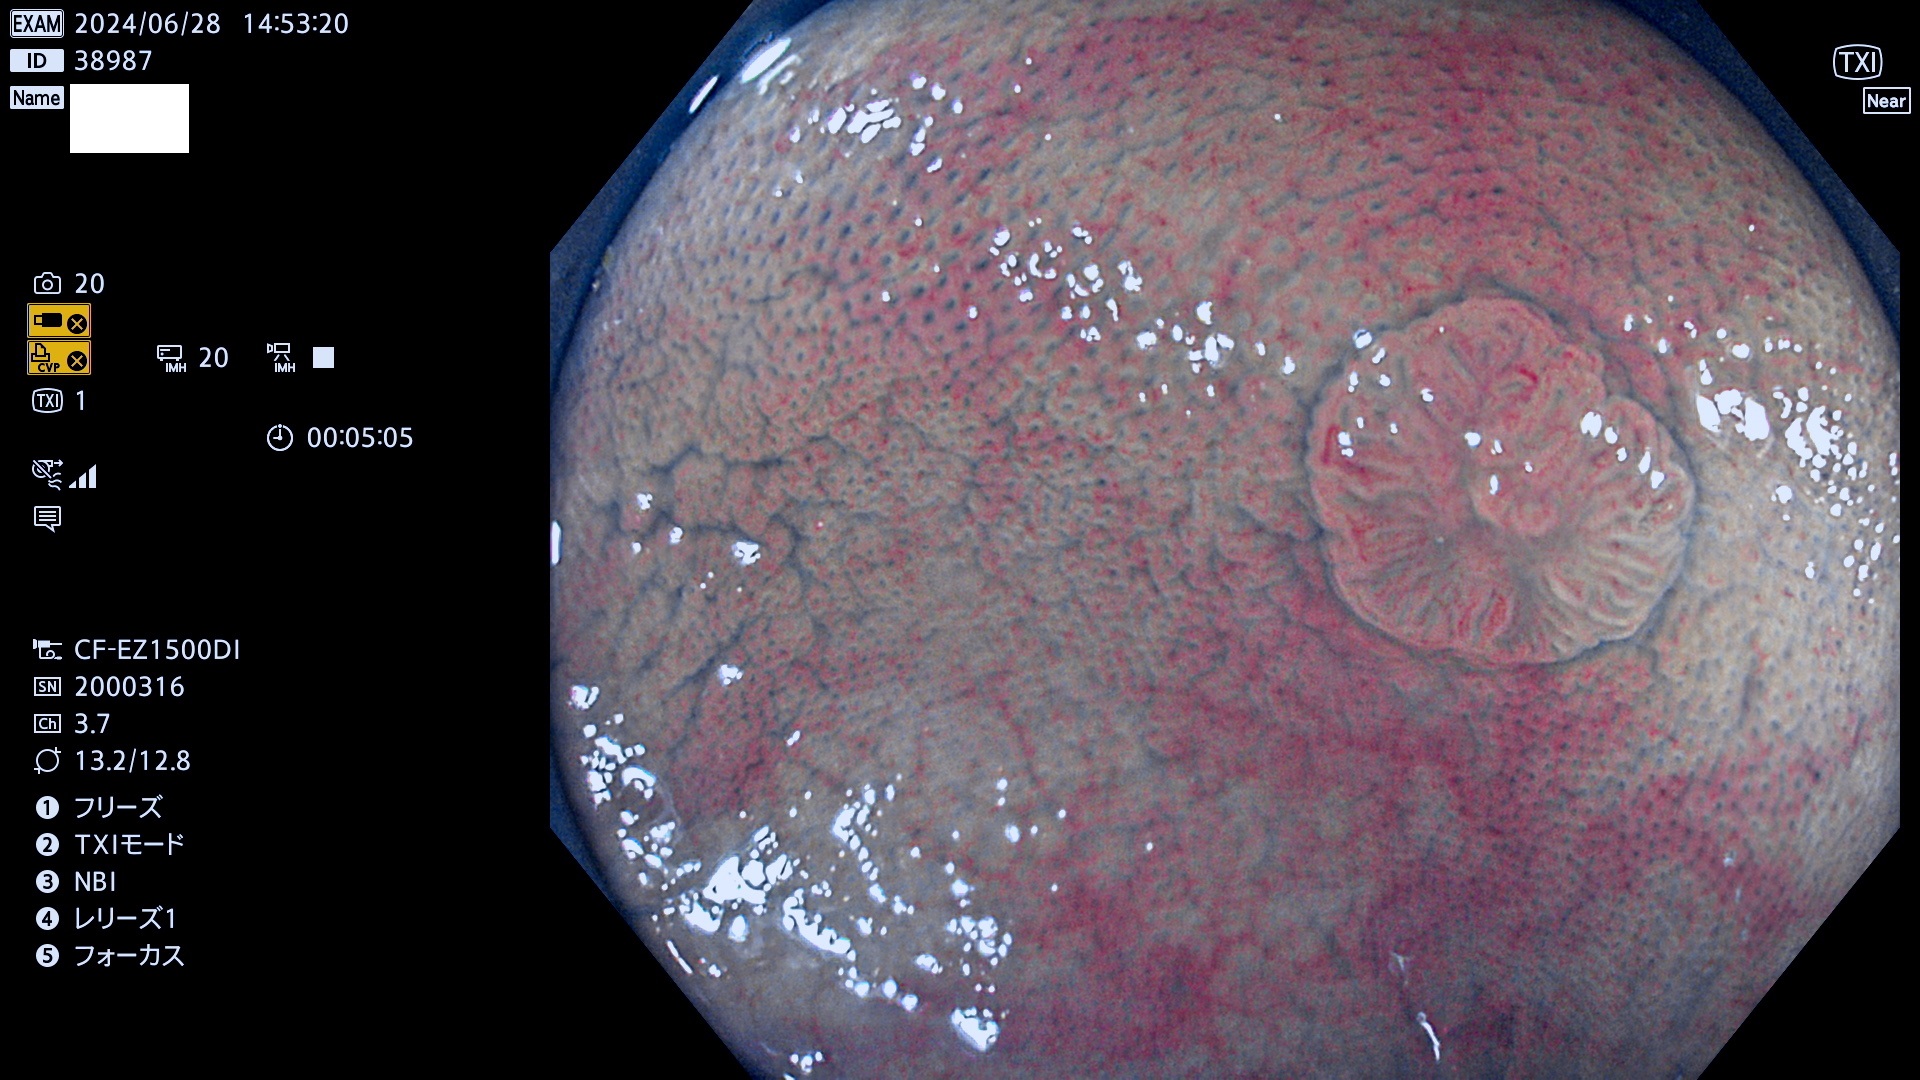

完全に平坦な物をUb、陥凹している物をUcと呼びます。最も発見が難しく危険な病変です。

抽出の対象期間 2024年6月27日〜7月1の5日間(40件の検査)6件 (6/40=15%)